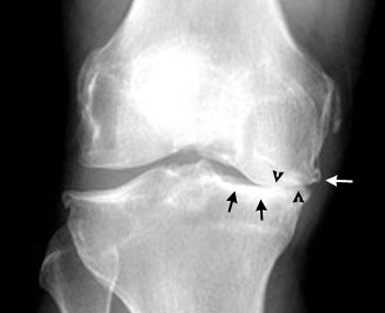

Osteoartritis koljena ili gonartroza je poremećaj hrskavice i periartikularne kosti koljena za koji ne postoji učinkovito medikamentozno liječenje. Neka istraživanja su sugerirala kako bi dodatak vitamina D u prehranu mogao pomoći u redukciji progresije ovog stanja, a istraživači s medicinskog centra Tufts u Bostonu su u studiji koja je objavljena u časopisu JAMA od 9. siječnja 2013 testirali ovu tezu. Randomizirana, placebo-kontrolirana, dvostruko slijepa studija koja je uključivala 146 ispitanika sa simptomatskim osteoartritisom koljena (srednja životna doba 62,4 god., 61% žena, 79% bjelačka populacija) provođena je u razdoblju između ožujka 2006. i lipnja 2009. godine. Ispitanici su podijeljeni u dvije skupine; jedni su primali placebo, dok su drugi primali 2000 IU na dan kolekalciferola peroralno kako bi se serumska doza povisila na više od 36 ng/mL. Glavni praćeni rezultati bili su bolnost koljena (WOMAC skala) i gubitak zglobne hrskavice mjereno magnetskom rezonancijom. Sekundarni rezultati mjerenja bili su: tjelesna funkcija, funkcija koljena (WOMAC skala funkcije), debljina hrskavice, lezije koštane srži te debljina zglobnog prostora. U konačnici je 85% pacijenata dovršilo tretman – u placebo grupi razina serumskog vitamina D povisila se za 2,1ng/mL, dok se u suplementiranoj grupi povisila za 16,1 ng/mL. Bol u koljenu na početku ispitivanja bila je blago lošija u suplementiranoj grupi, dok je funkcija koljena bila značajno lošija u suplementiranoj u odnosu na placebo grupu. Bol u koljenu se smanjila u obje grupe, pri čemu je smanjenje bilo nešto izraženije u suplementiranoj (-2,31), nego u placebo grupi (-1,46). Gubitak hrskavice nakon razdoblja praćenja bio je podjednak u obje grupe. Nije bilo razlike ni u jednom od sekundarnih rezultata mjerenja. Na temelju navedenog može se zaključiti kako suplementacija vitaminom D u razdoblju od dvije godine, koja povisuje serumsku razinu vitamina D do 36 ng/mL, ne smanjuje značajno bol u koljenu ili gubitak zglobne hrskavice. |